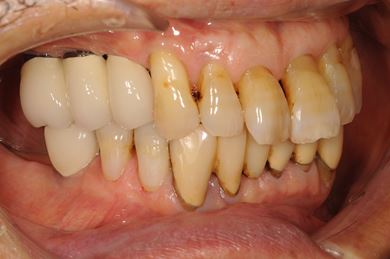

| 性別/年齢 | 男性 / 67歳 | ||||||||||||||||||||||||||||||||

| 主訴 | 欠損部分のインプラント・差し歯治療を希望。 | ||||||||||||||||||||||||||||||||

| 治療内容 | インプラント8本(サイナスリフト、ソケットリフト、GBR)、メタルボンドセラミック8本 | ||||||||||||||||||||||||||||||||

| 総治療費 | 3,711,540円 | ||||||||||||||||||||||||||||||||

| 治療期間 | 1年5ヶ月 |